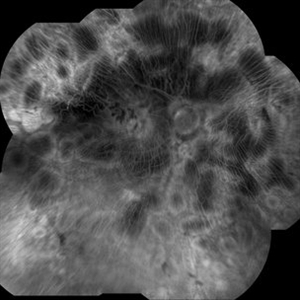

Sickle Cell Retinopathy with Sea Fans (angiogram)

Fluorescein angiography (late phase) of a 40-year-old man with African heritage and sickle SC disease. Sea fans are present around the macula (profusely leaking fluorescein dye).

Photographer: Geoffrey Emerson, MD, PhD, Retina Center, Minneapolis

Condition/keywords: sea fan